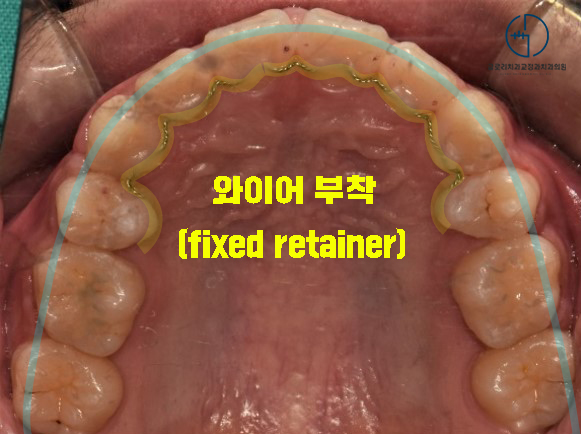

브라켓 제거 후,

현재 모습을 유지해 줄 와이어(fixed retainer)를

안쪽에 부착했습니다.